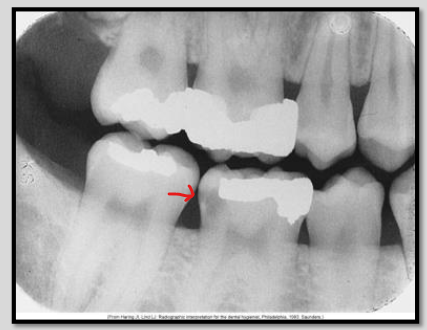

What class of interproximal caries is this?

Class 3 Advanced